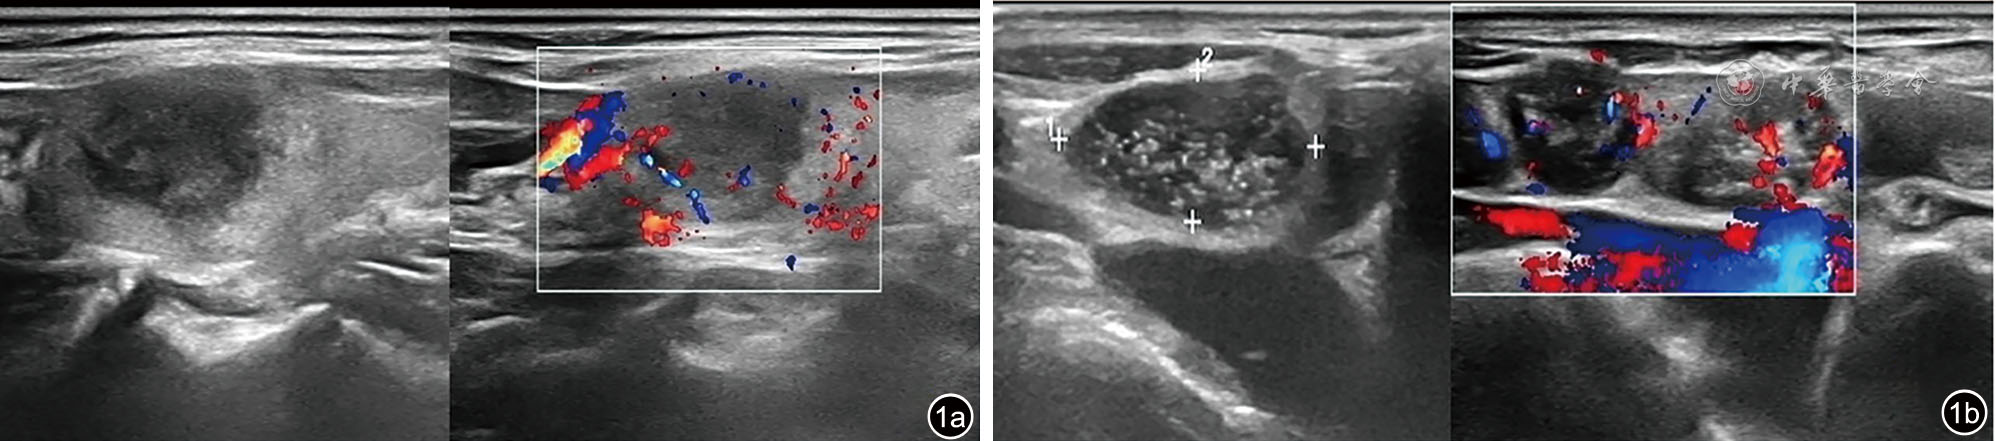

图1 甲状腺结核二维超声及彩色多普勒血流成像(CDFI)图像(图a)及右颈部淋巴结二维超声及CDFI图像(图b)